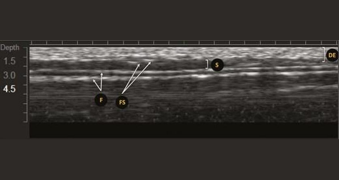

Image échographique obtenue avec un transducteur MFU-V. Le derme et l’épiderme (DE), le fascia (F), les septaes fibreuses (FS) et les adipeux sous-cutanés (SA) sont représentés.